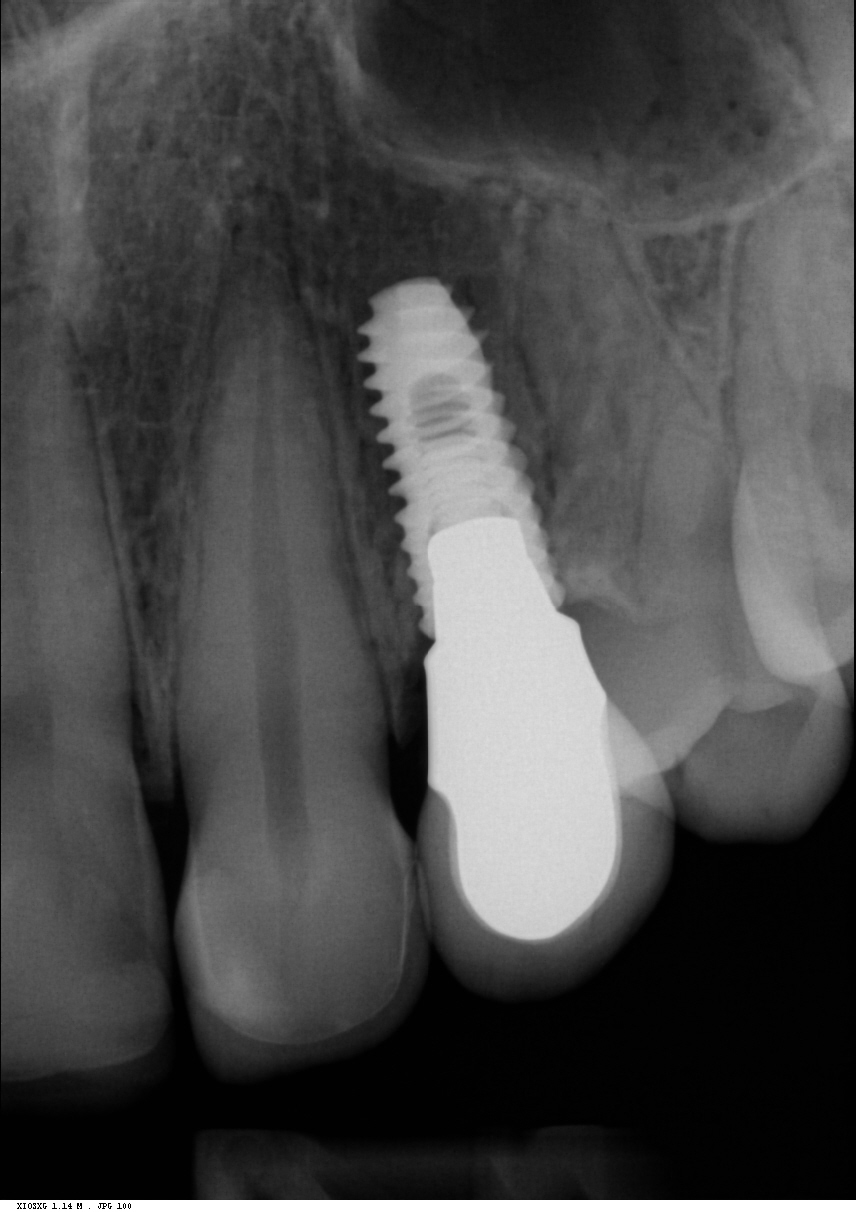

Implantit paikoillaan 1/3

Implantit paikoillaan 2/3

Implantit paikoillaan 3/3

Radiologinen näkymä lopputilanteesta. Implanttikruunut paikoillaan.

Sama tilanne toiselta puolelta